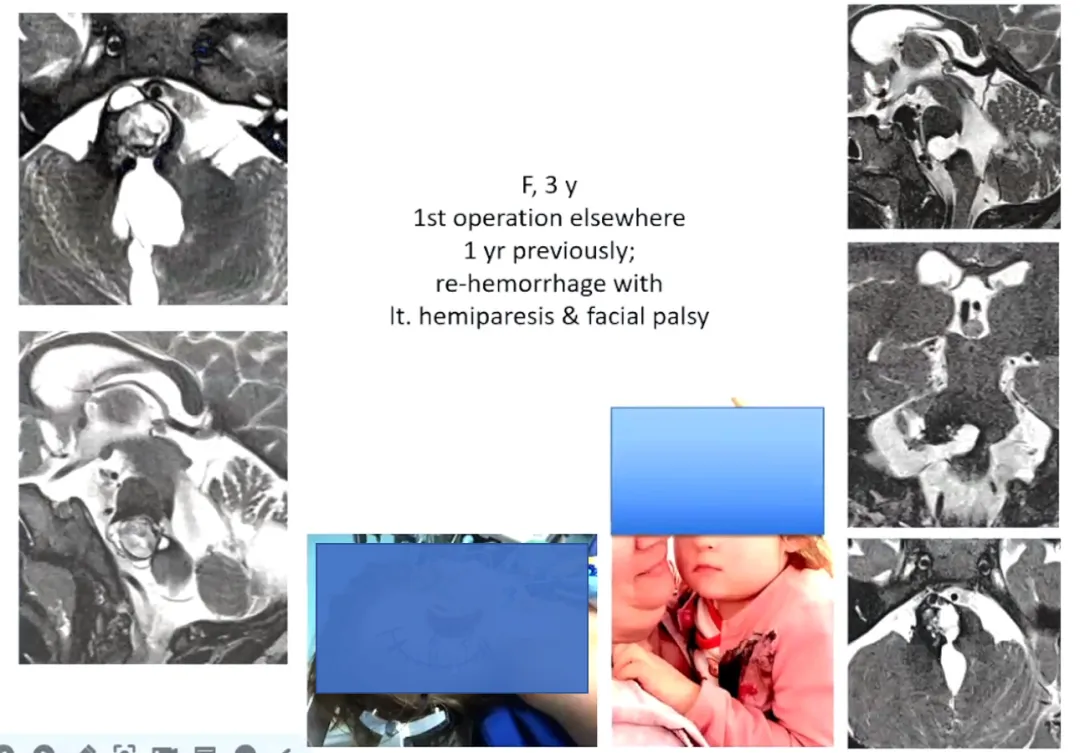

三岁患儿米娜:外院术后残留病灶,出现外展神经麻痹和面瘫。经巴教授再次手术全切病灶,预后良好。